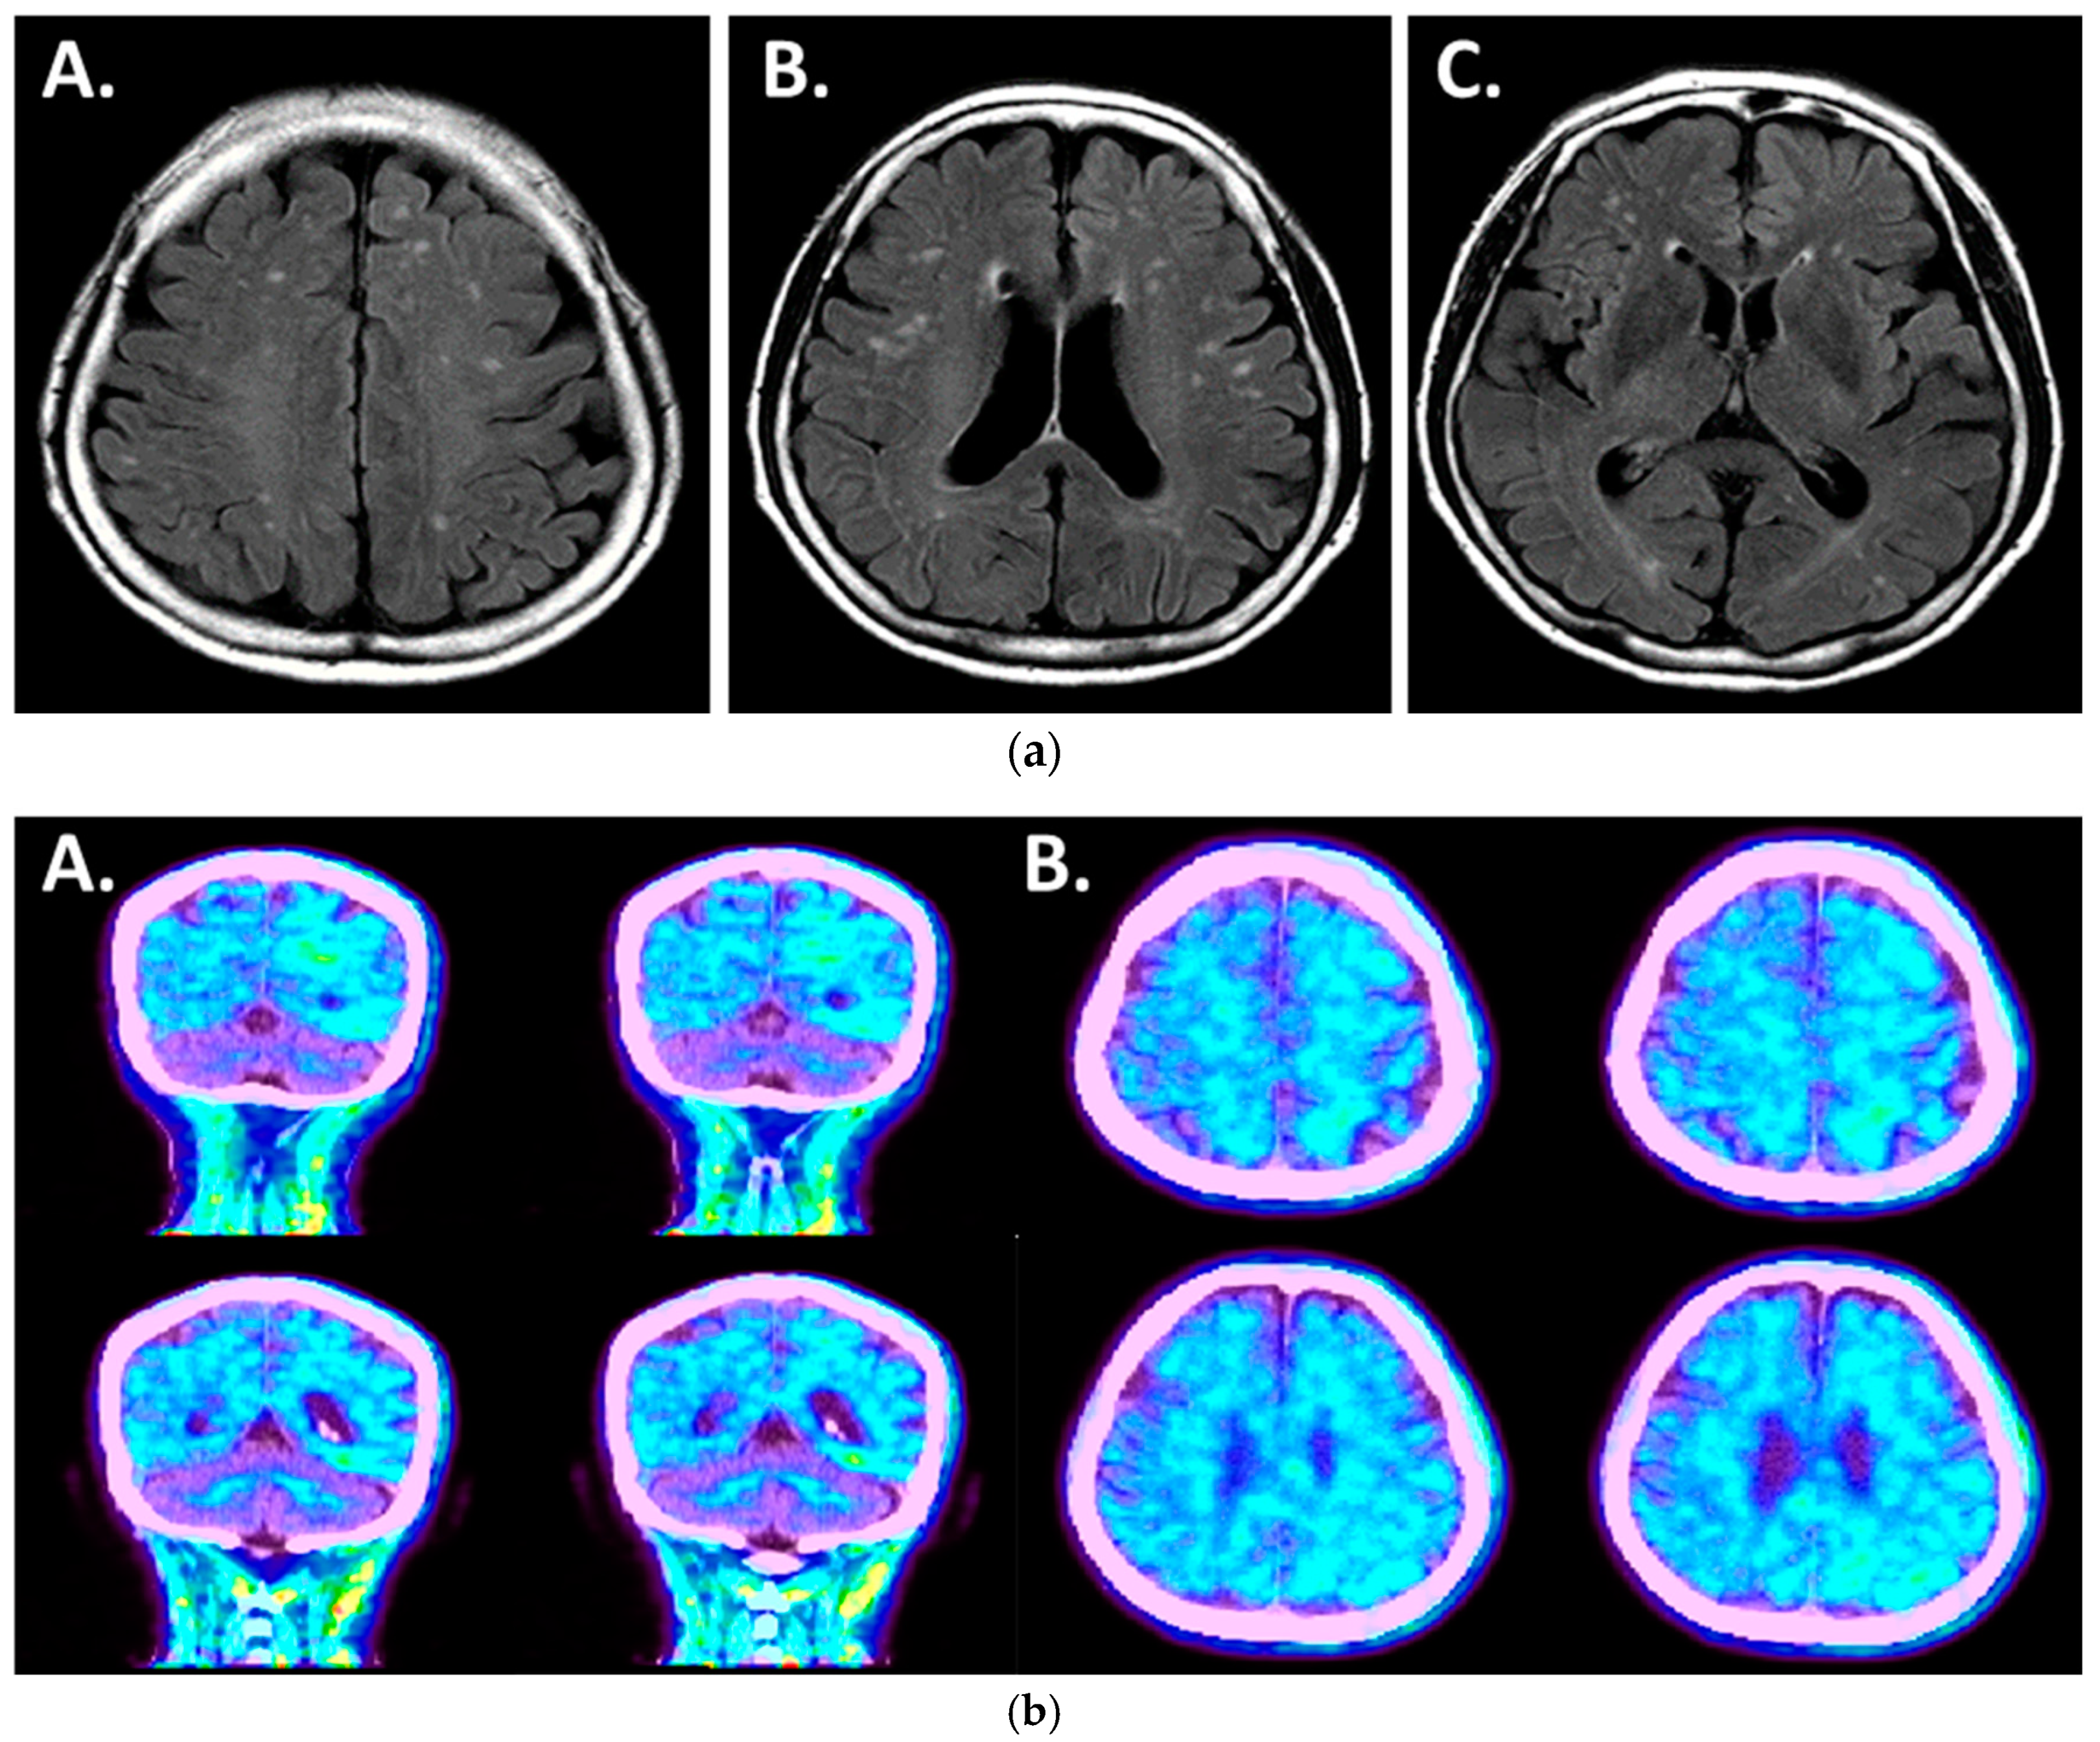

| Val226Ala | AD with hallucinations | 59 | NA | Positive in both Amyloid PET and plasma OAβ | NA | Current case |